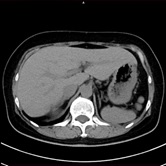

単純CT画像          造影CT画像          MPR画像